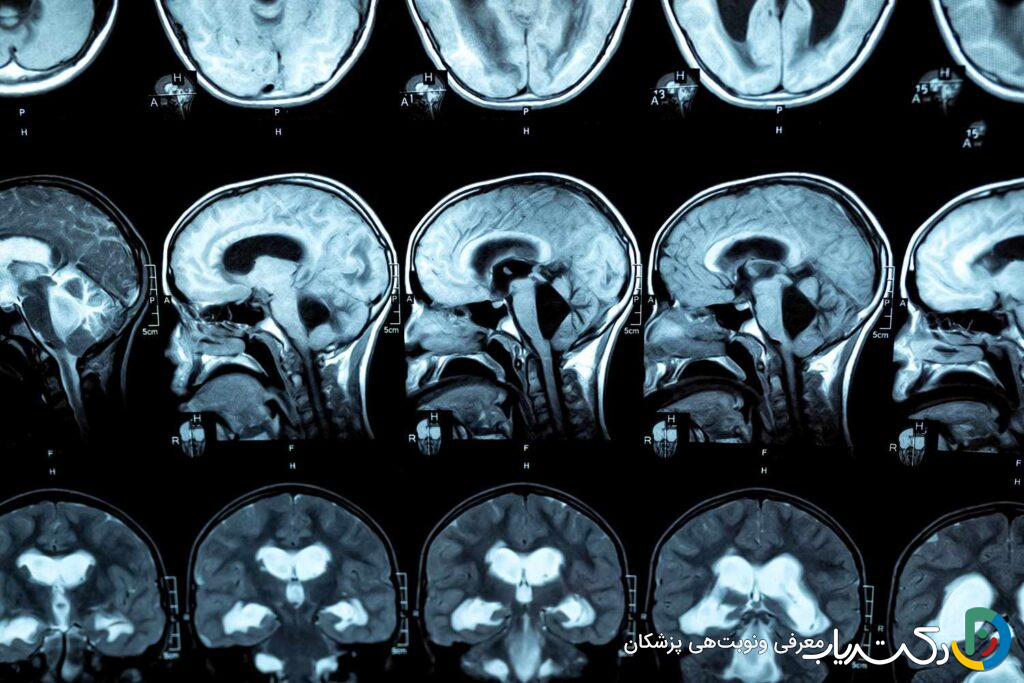

تکنیکهای تصویربرداری مغز

تصویربرداری از مغز برای تأیید قطعی تشخیص، شناسایی علت زمینهای (مانند انسداد) و تعیین شدت هیدروسفالی کاملاً ضروری است.

- سونوگرافی جمجمه: یک روش ایمن، غیرتهاجمی و سریع برای نوزادان است که میتوان از طریق ملاج باز آنها انجام داد. این روش به خوبی اندازه بطنهای گشادشده را نشان میدهد و برای غربالگری اولیه و پیگیری پس از درمان بسیار مفید است. سونوگرافی در دوران بارداری (سونوگرافی پرهناتال) نیز میتواند هیدروسفالی را در جنین تشخیص دهد.

- تصویربرداری رزونانس مغناطیسی (MRI): این روش استاندارد طلایی برای تشخیص هیدروسفالی است. MRI بدون استفاده از اشعه ایکس، تصاویر بسیار دقیق و با جزئیات بالا از ساختار نرم مغز، بطنها و مسیرهای جریان CSF ارائه میدهد. این روش میتواند علت دقیق انسداد (مانند تومور، کیست یا تنگی مجرا) را مشخص کرده و به جراح در برنامهریزی بهترین روش درمانی کمک کند.

- توموگرافی کامپیوتری (CT Scan): سیتی اسکن سریعتر از MRI است و در شرایط اورژانسی (مانند ضربه به سر) برای ارزیابی سریع اندازه بطنها و وجود خونریزی بسیار مفید است. با این حال، به دلیل استفاده از اشعه ایکس، برای پیگیریهای مکرر در کودکان کمتر ترجیح داده میشود.